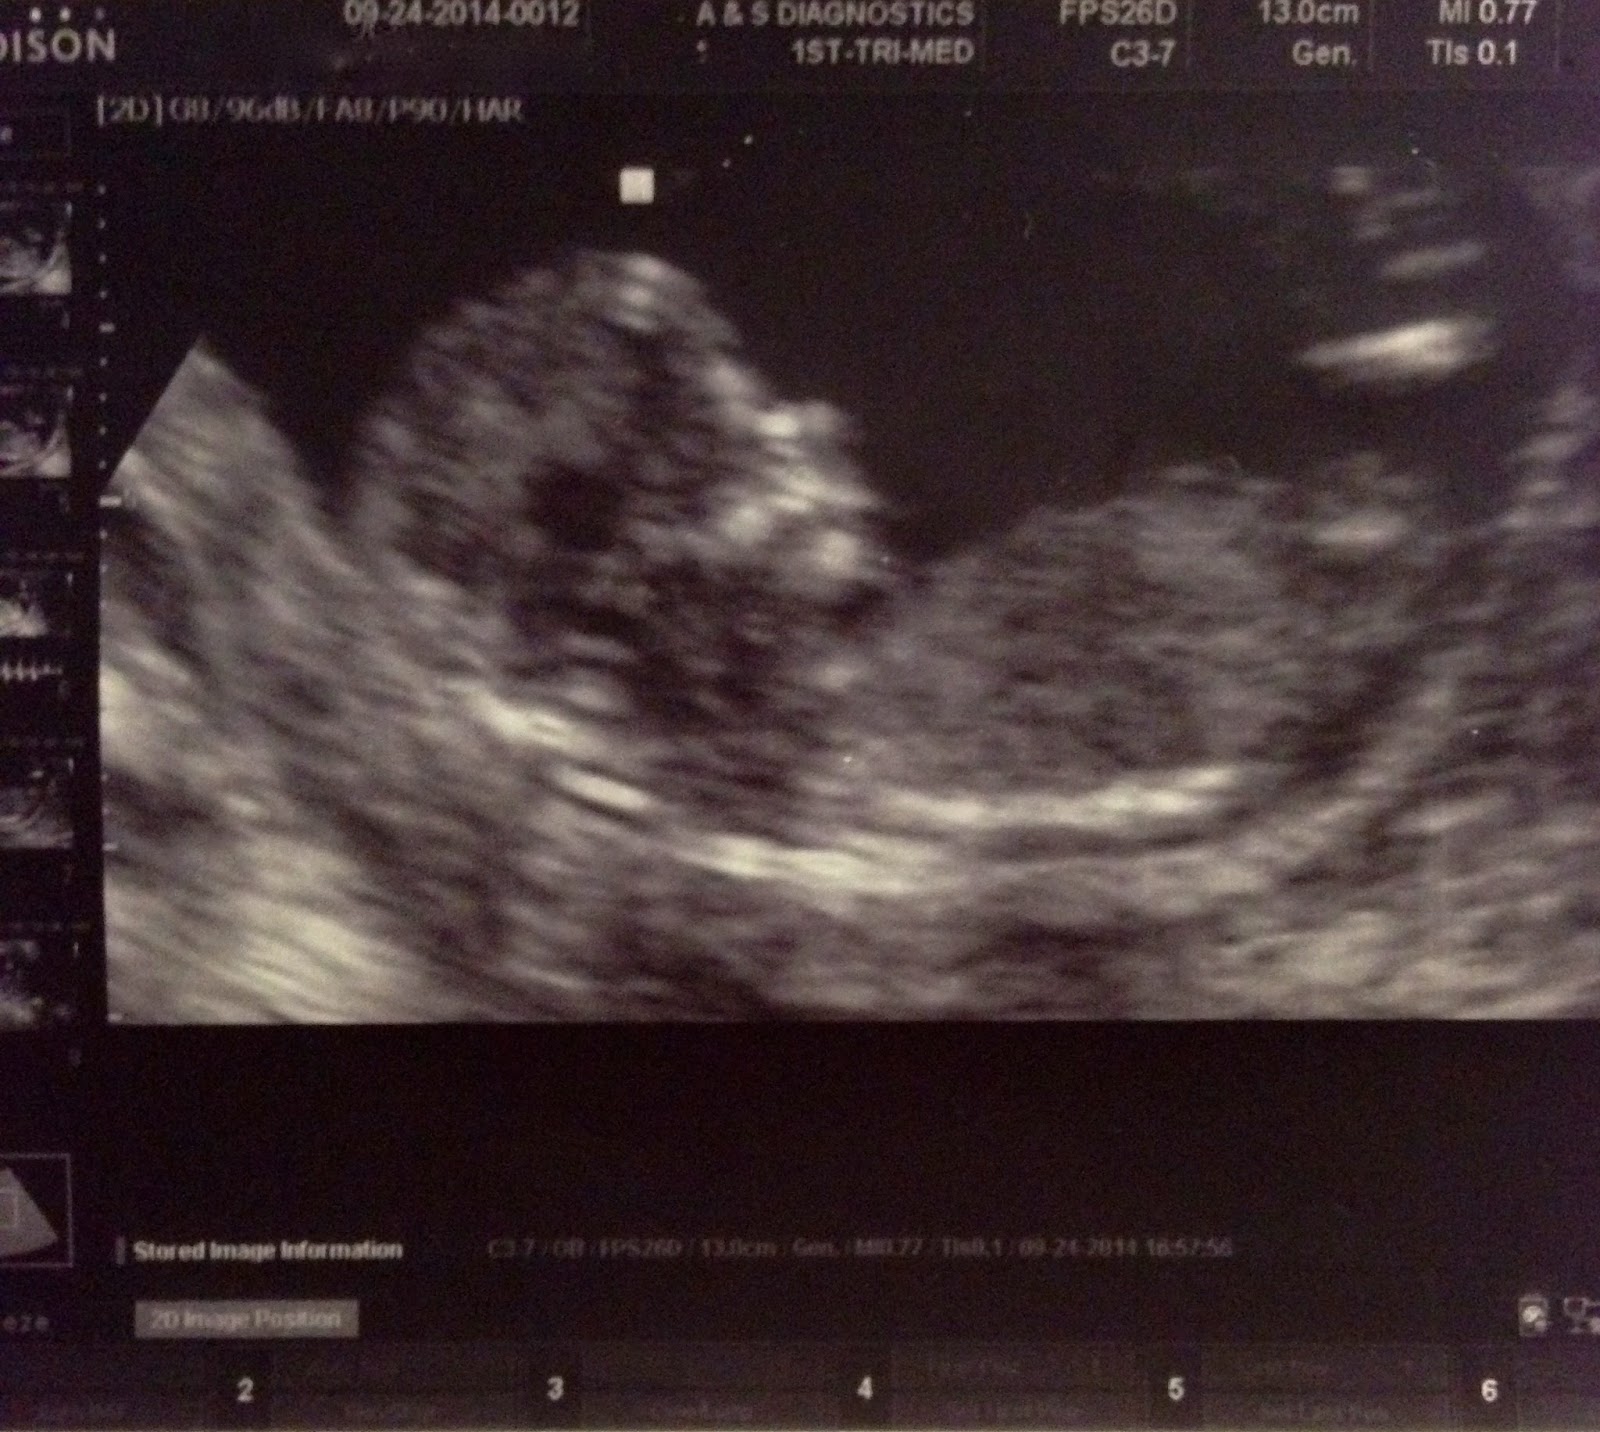

We were finally able to tell the world about you this week and everyone is so excited to meet you. At your last ultrasound, you finally looked like an actual baby with a profile, arms and legs! You were so active, moving around your little arms, and the sound of your heartbeat is one of the most beautiful sounds I’ve ever heard. The next day, we found out you’re a BOY! Lucky you, because you’re going to have so many boy cousins to play with!

How far along? 13 weeks! Finally out of the first trimester. 26 more weeks to go.